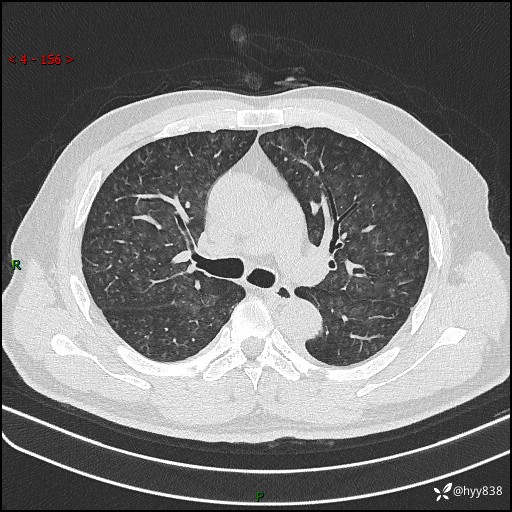

昨天肺结节门诊,“对门”呼吸科申请会诊病例,弥漫性肺部病变---结果公布~

简要病史:患者1周前无明显诱因出现咽喉部疼痛,随后出现咳嗽咳痰,起初干咳为主,后出现咳少许绿色痰,当时有发热,体温为39℃,无畏寒寒战,无胸闷胸痛,无活动后气短,无咯血,无鼻塞流涕,无全身酸痛,患者于诊所输液治疗后体温正常,但仍有咳嗽。患者3天前当地县人民医院就诊,患者仍有咳嗽,咳嗽较为频繁,咳嗽后出现头痛,伴有少许咳痰,随后出现活动后气短,1天前患者再次出现发热,体温最高为40℃,伴有畏寒寒战,伴有乏力、纳差,伴有胸闷不适,无咯血,无全身皮疹,无血尿、尿频尿急尿痛,无腹泻,诊断为“重症肺炎 感染性休克 肾功能异常 痛风”;予以抗感染(亚胺培南),抗病毒(奥司他韦)等对症治疗。患者复查胸部CT提示双肺病灶较前有所增多,建议上级医院就诊,门诊以“肺部感染”收入我科。 起病以来,患者食欲欠佳,大小便正常,睡眠、精神欠佳,体力下降、体重无明显变化。

辅助检查:CT

临床诊断:肺部感染

胸部HRCT